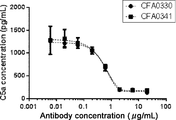

- Figure 9A illustrates inhibition of complement-activated liposome lysis by anti-C5 antibodies, as described in Example 5.1.

- Figure 9B illustrates inhibition of complement-activated liposome lysis by anti-C5 antibodies, as described in Example 5.1.

- the results of antibodies CFA0330 and CFA0341 grouped into epitope B, as described in Example 2.2, are shown.